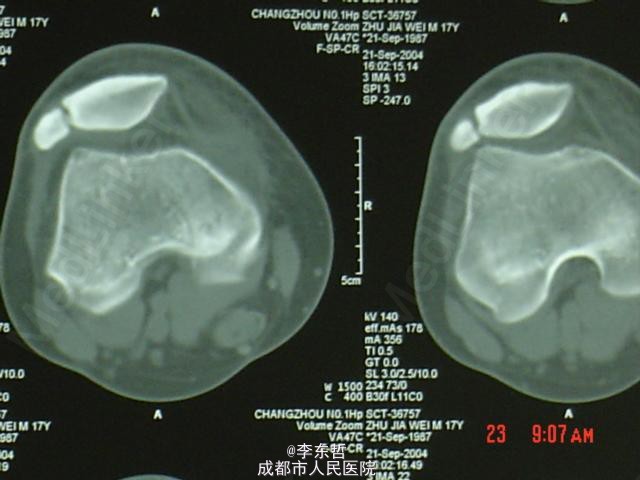

髌骨矢状位骨折

患者男,17岁,车祸致伤右膝,肿胀疼痛,能下地行走,考虑但病人年龄小,骨折愈合快,给予患肢功能位固定6周。